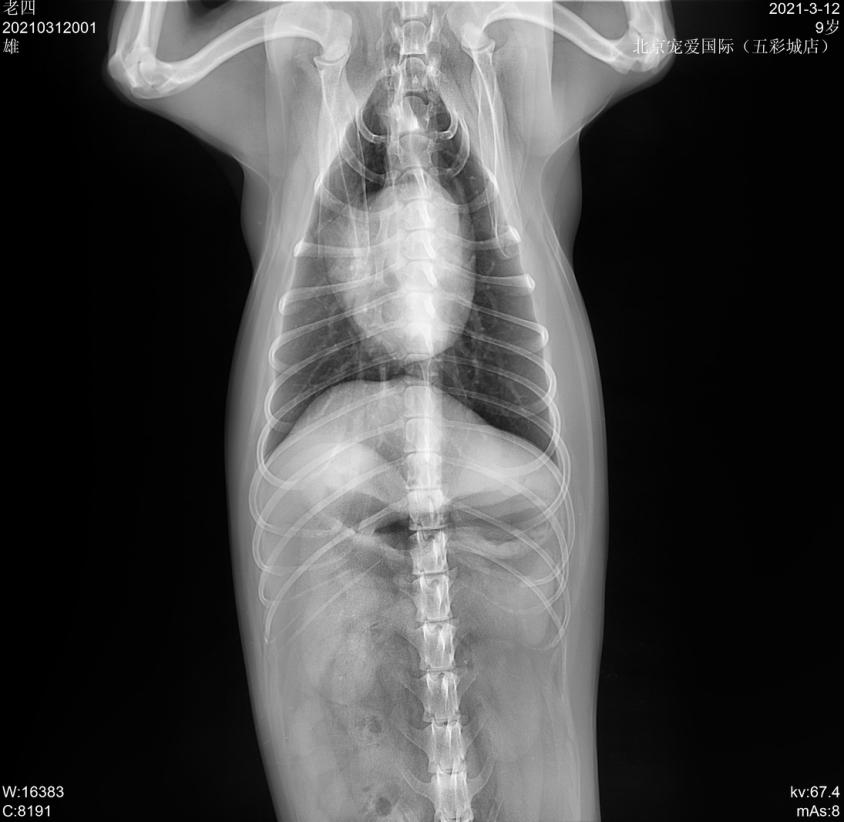

x线检查

临床检查: TPR正常,精神沉郁,步态缓慢,肛门左侧有一大的鼓包,较软; 直肠检查肛周左侧有一疝孔。

会阴疝